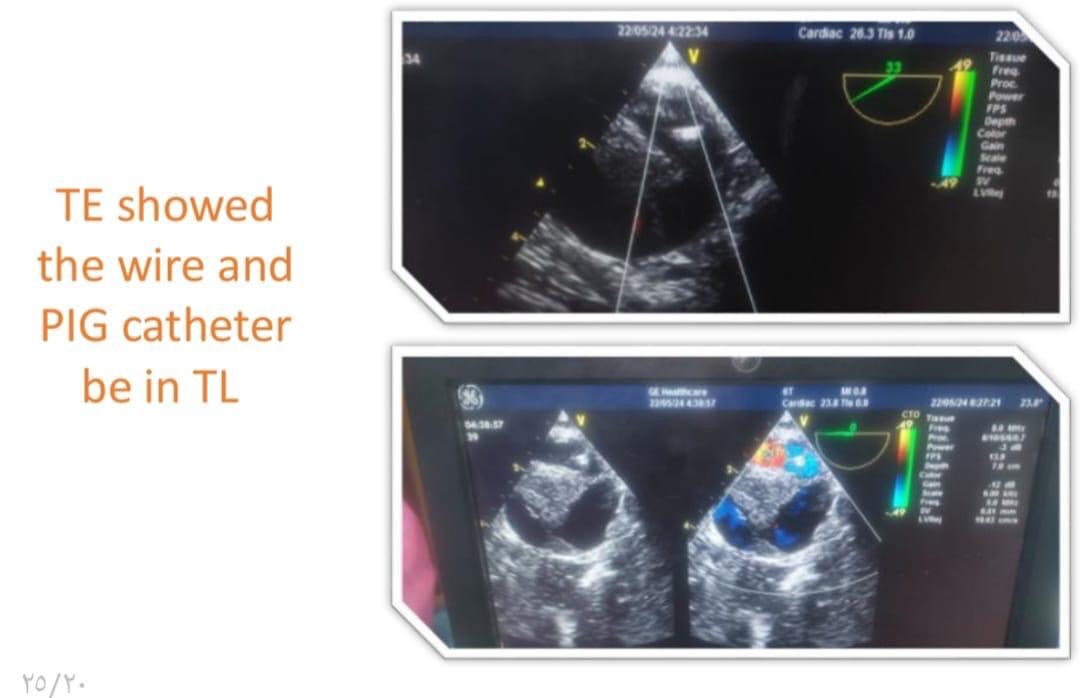

وتابع البيان، بناءً على التقييم الطبي للحالة تقرر إجراء تدخل مزدوج حيث تضمنت المرحلة الأولى إجراء عملية قلب مفتوح لاستبدال الشريان الأورطي الصاعد وإعادة توصيل شرايين الرقبة باستخدام شرايين صناعية، فيما شملت المرحلة الثانية تركيب دعامات مغطاة بالشريان الأورطي وقوسه باستخدام تقنية TEVAR وغلق الشريان تحت الترقوة باستخدام سدادة عبر القسطرة التداخلية تحت توجيه الأشعة التلفزيونية عن طريق المريء وتم تنفيذ التدخلين باستخدام أحدث التقنيات الطبية وبكفاءة عالية أسفرت عن تحسن ملحوظ في حالة المريض الذي غادر المستشفى بعد أسبوع من المتابعة الدقيقة وهو بحالة مستقرة الآن.